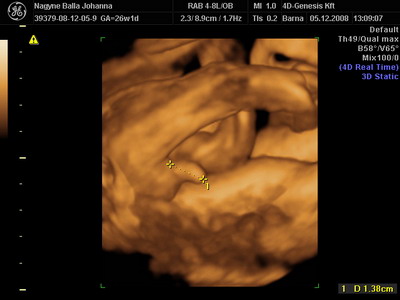

Nem direkt mérettük a fütyijét..

Csilla, az uh-s hölgy volt nagyon jó fej. Kérdezte, tudjuk-e ki lakik a pociban, mondtuk, kisfiú. Erre azt mondta, nézzünk rá. Kereste, Lukács mutatta, kis fütyi így, kis fütyi úgy, aztán fordult a kép, és Csilla nagy nevetve, nem is kicsi annyira ez a kis fütyi!

Akkor mérte le!